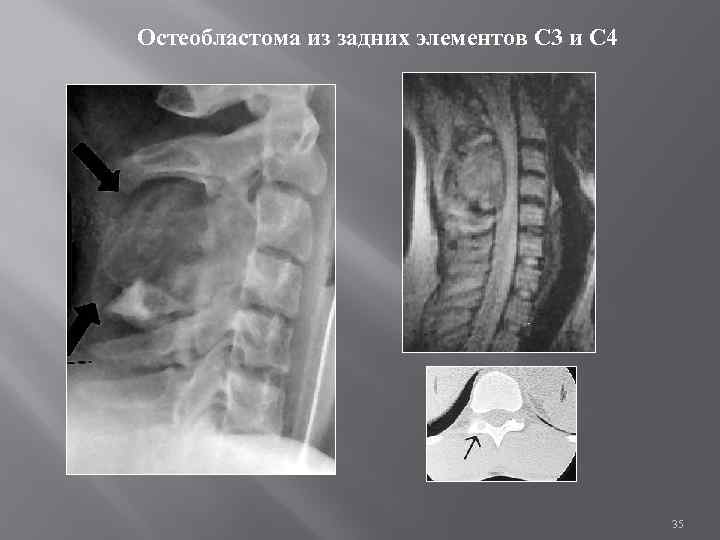

Спондилография Опухоли из позвоночного канала объемные процессы в позвоночном канале, СМ, оболочках расширение позвоночного канала расширение м/п отверстий деструкция дужек Симптом Элсберга - Дайка для экстрамедуллярной опухоли атрофия корней дужек позвонков увеличение расстояния между ними Изменения метастатической опухоли позвонков Синдром Клиппеля – Фейля : срастание нескольких шейных позвонков 34

Остеобластома из задних элементов С 3 и С 4 35